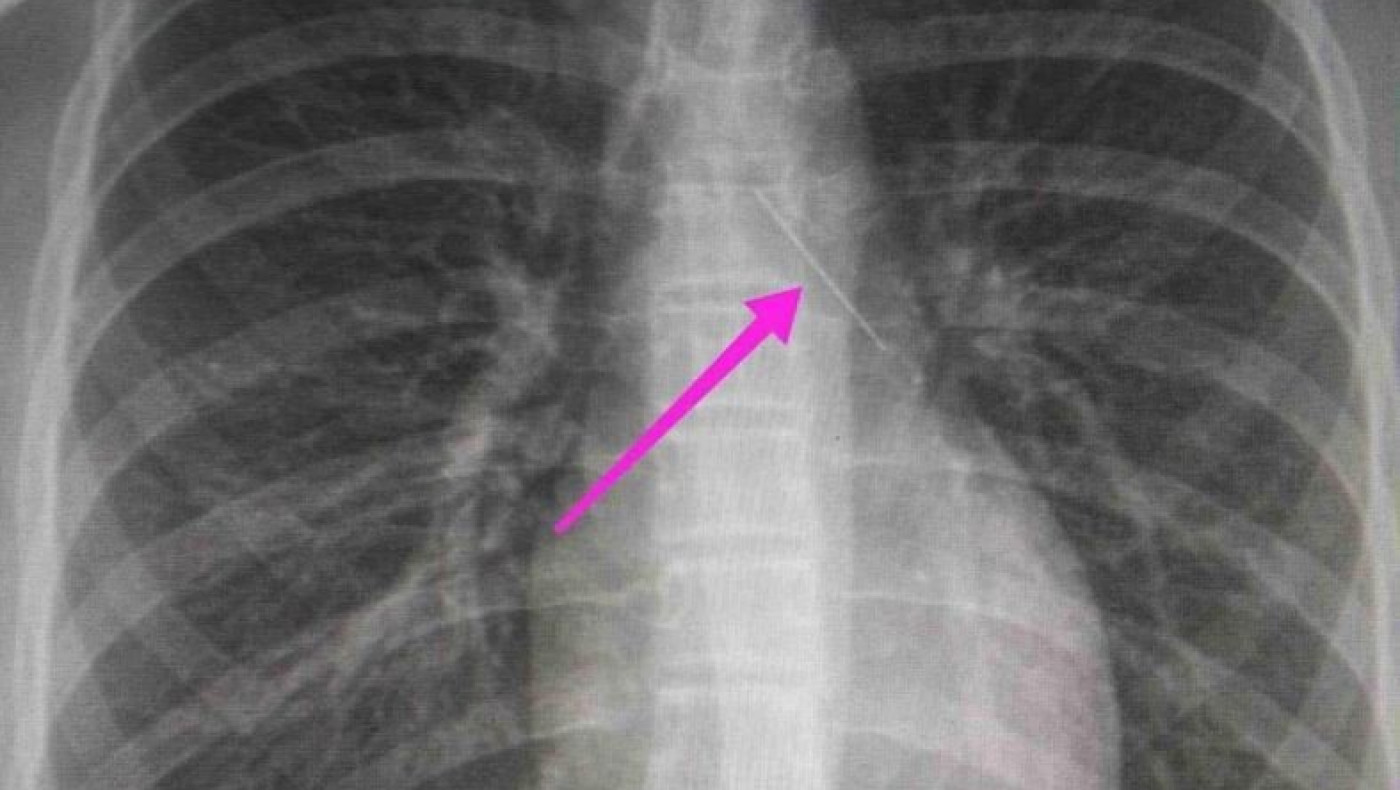

Από την απεικονιστική διερεύνηση που πραγματοποιήθηκε με ακτινογραφία θώρακος αρχικά και ακολούθως με αξονική τομογραφία θώρακος, διαπιστώθηκε η ύπαρξη αιχμηρού μεταλλικού ξένου σώματος στην αναπνευστική οδό (αριστερός κύριος βρόγχος) και όχι στην πεπτική οδό, αναφέρει η ανακοίνωση του νοσοκομείου, στα μέσα κοινωνικής δικτύωσης.

Η ανήλικη υπεβλήθη σε βρογχοσκόπηση και διαπιστώθηκε η μετακίνηση και ενσφήνωση της καρφίτσας στον δεξιό κύριο βρόγχο. Μετά οπό εργώδεις προσπάθειες ολοκληρώθηκε με επιτυχία η αφαίρεσή της.